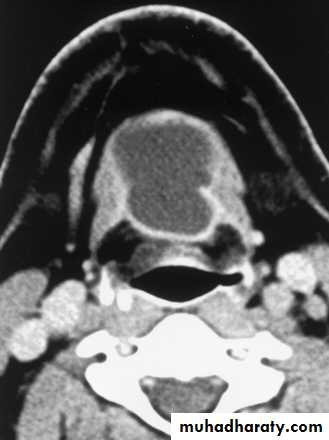

Computed Tomography

Distinguish cystic from solidExtent of lesion

Vascularity (with contrast)

Detection of unknown primary (metastatic)

Pathologic node (lucent, >1.5cm, loss of shape)

Avoid contrast in thyroid lesions

14

15